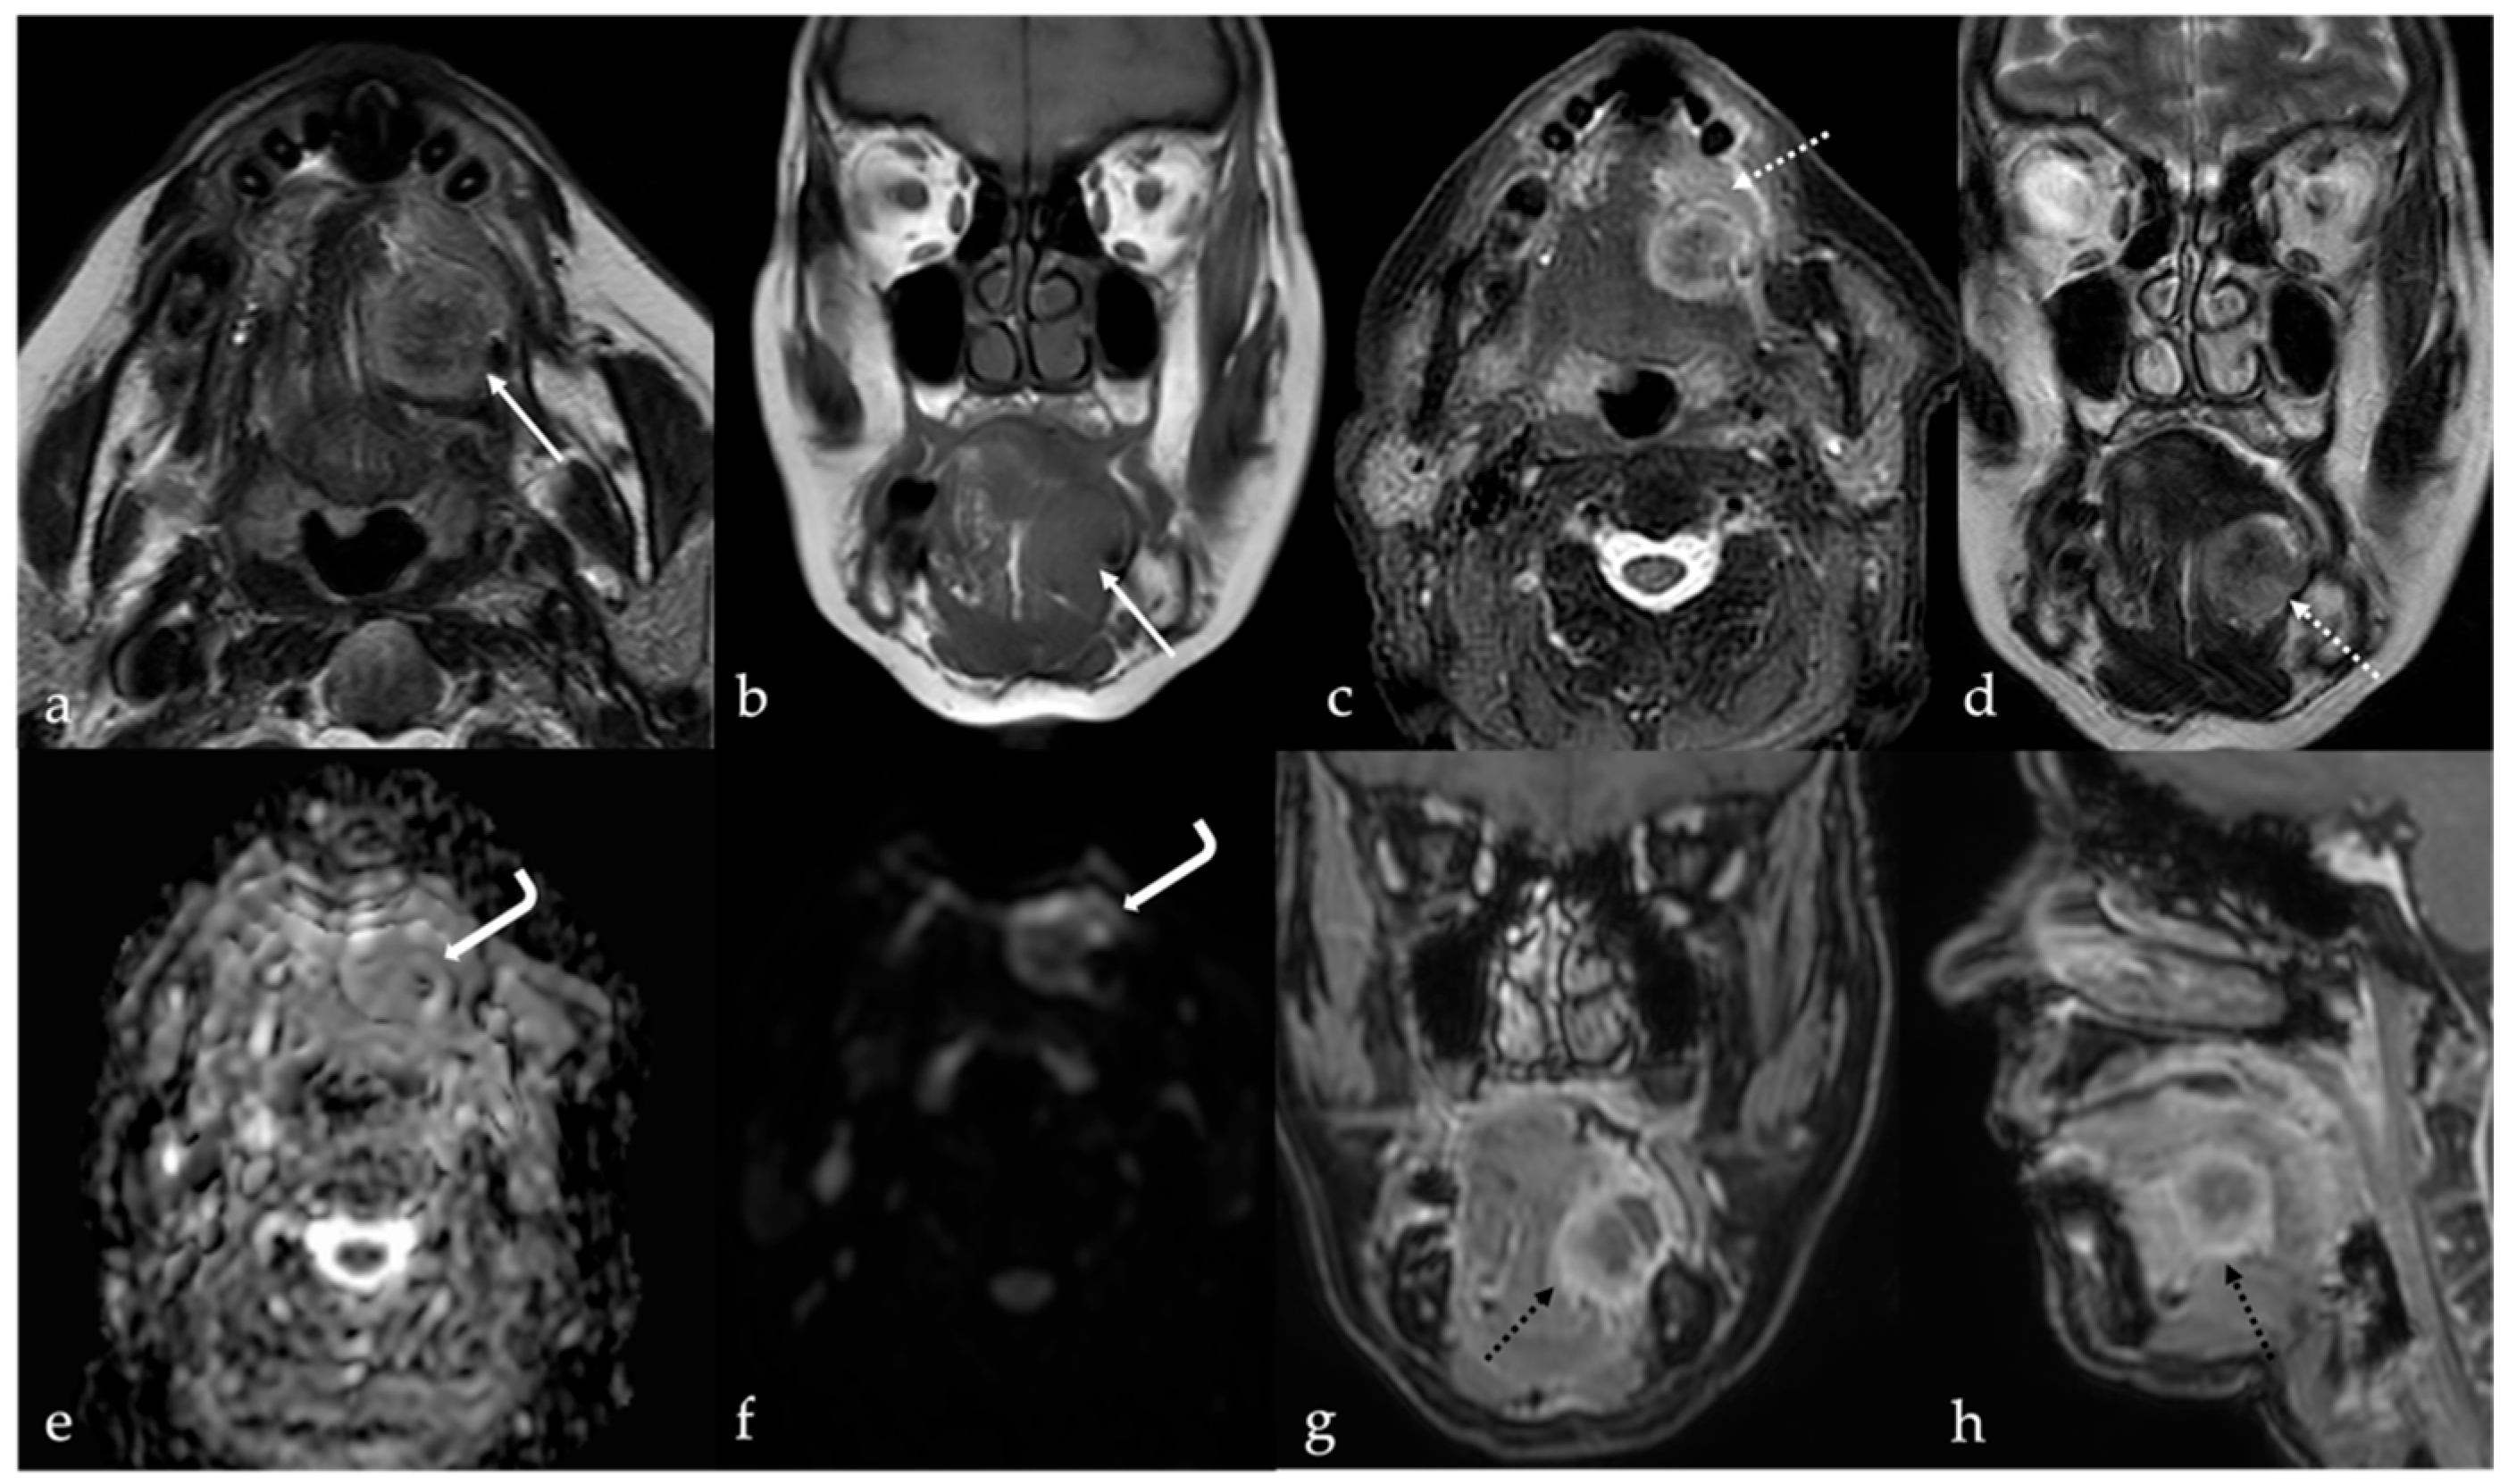

5. Vascular Malformations and Tumors

5.1. Venous Malformations

| Venous malformation [1,9] | CT: phleboliths MRI: high T2 SI, +CE | Other vascular malformations, schwannoma, dermoid cysts |